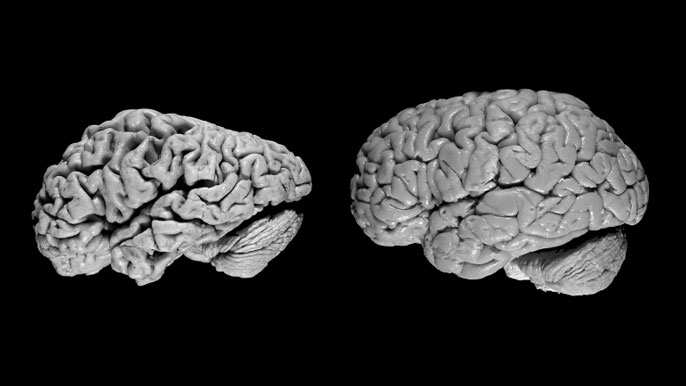

Radiologists have used these scans to try to detect Alzheimer’s by looking for reduced glucose levels across the brain, especially in the frontal and parietal lobes of the brain. However, because the disease is a slow progressive disorder, the changes in glucose are very subtle and so difficult to spot with the naked eye.

To solve this problem, Sohn applied a machine learning algorithm to PET scans to help diagnose early-stage Alzheimer’s disease more reliably.